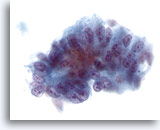

膵FNA、膵腺癌

膵腺癌の吸引組織にみる悪性細胞。疎な結合を示す集塊を形成し、異型細胞が孤立性に散在しています。

20倍

画像 74

膵FNA、膵腺癌

膵腺癌の吸引組織にみる悪性細胞。疎な結合を示す集塊を形成し、異型細胞が孤立性に散在しています。

20倍